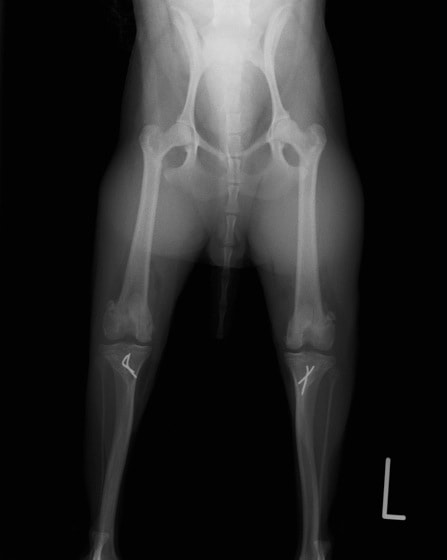

■ 症例20 ポメラニアン 8ヶ月 1.8kg

左右膝蓋骨脱臼 グレードⅢ

2ヶ月前から間欠的跛行が認められ、両膝の膝蓋骨脱臼整復術を行った。

手技は縫工筋及び内側広筋の解放、脛骨粗面の外側転位、滑車ブロック形造溝術、内外側関節包の縫縮を選択し実施した。

右側の膝蓋骨脱臼は上記手技で整復されたものの、左側はそれのみでは膝蓋骨が浮く様子が認められた。その為、PDS縫合糸にて膝蓋靱帯を1糸のみ縫合し、靱帯の縫縮を行った。

膝蓋骨脱臼は膝関節における膝蓋骨の内外側の脱臼と定義されるが、時として単純な内外の脱臼ではなく、膝蓋骨が大きく前方に浮き上がるように脱臼する場合がある。特にトイプードルやポメラニアンといった犬種に多く認められる。

内側脱臼に加えて前方への浮き上がりを矯正する為に、従来より脛骨粗面転移により膝蓋靭帯を外方と下方に引っ張り、固定する方法を選択する。膝蓋骨の前方への浮き上がりが軽度の場合は、従来法ではなく関節包の縫縮で対応していた。しかし、一部の症例で膝蓋骨の動きが悪くなり伸展機構が円滑に機能せずロボット様歩行になるケースがあった。

その為、膝蓋靭帯自体を縫縮する方法を採用した。この方法により、膝関節の伸展機構を妨げず膝蓋骨の軽度の浮きを矯正することが可能となった。

本症例の経過は良好である